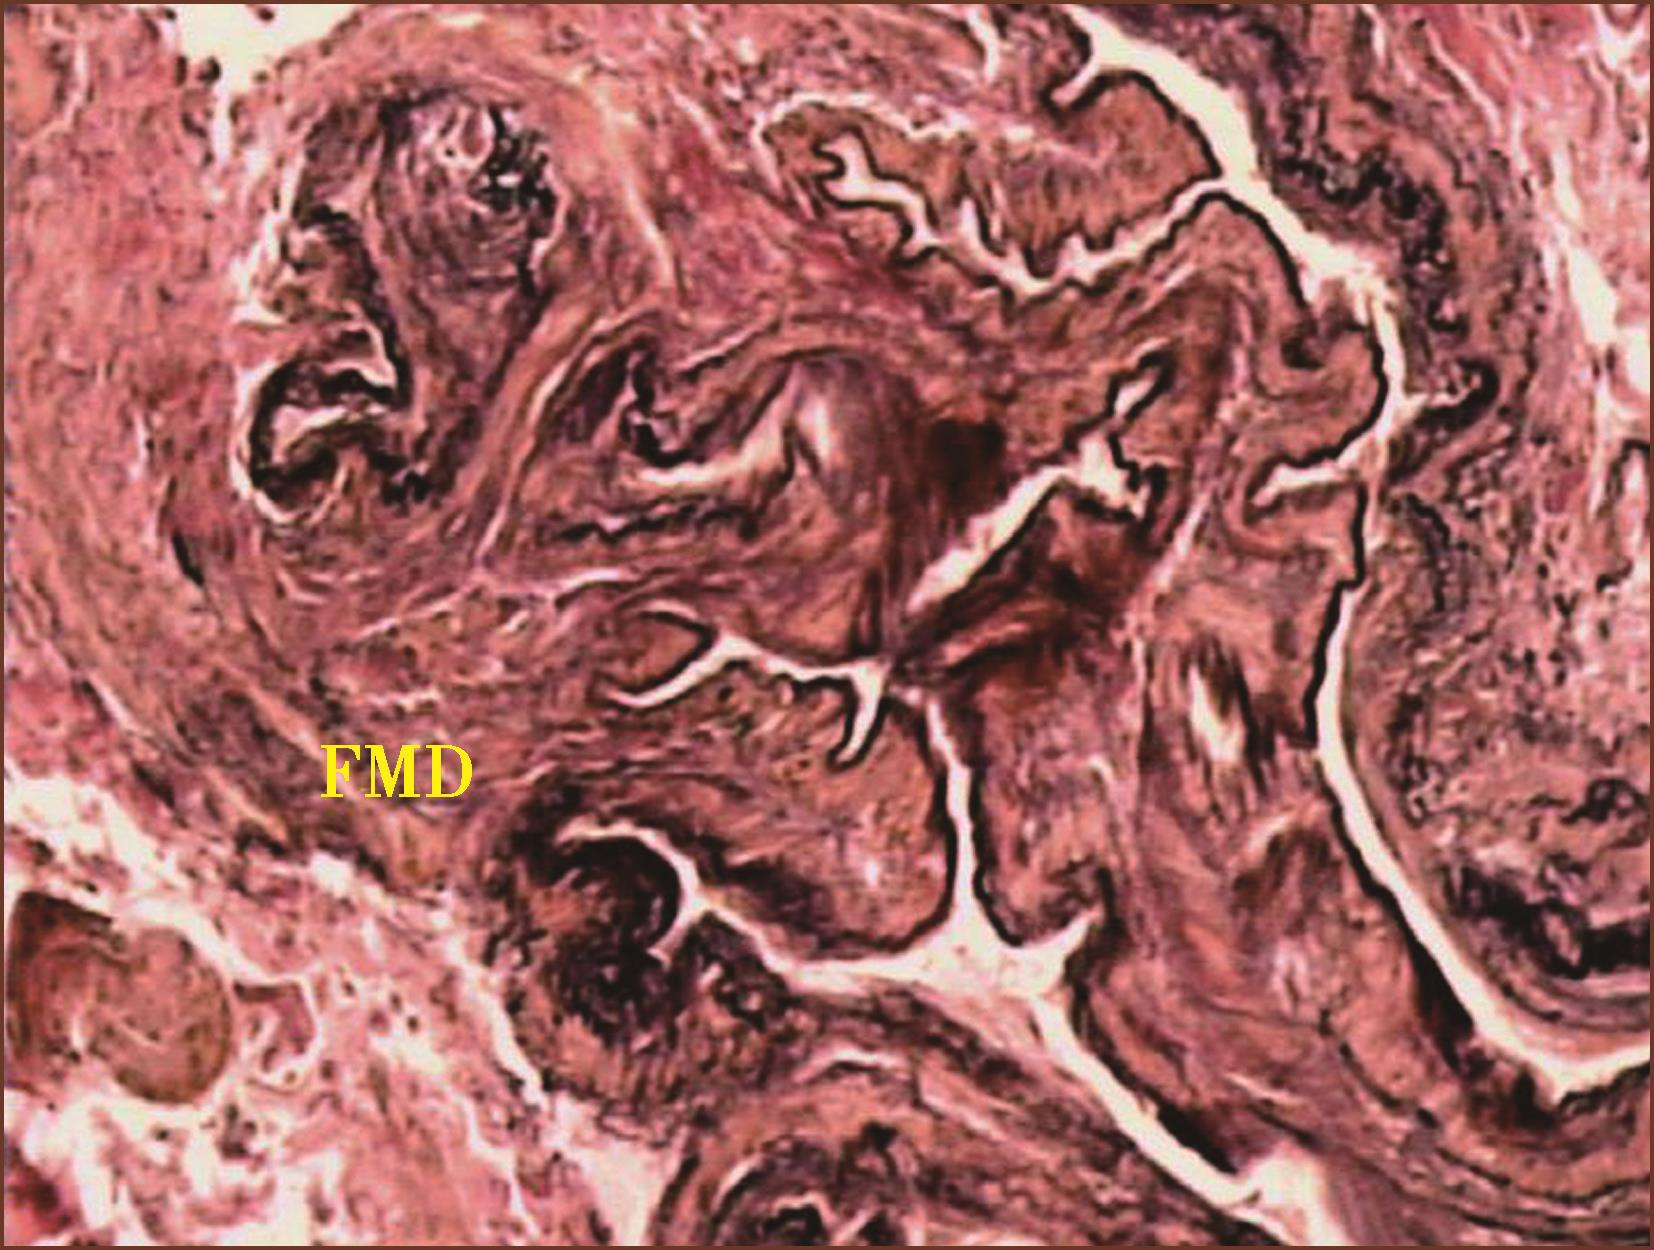

1.肺小动脉纤维肌性结构不良(pulmonary fibromuscular dysplasia,FMD)

肺小动脉纤维肌性结构不良患者临床及影像学检查表现为不明原因的肺动脉高压。光镜组织学检查,发现肺肌型动脉中层肥厚,中膜肌纤维、胶原纤维及弹力纤维异常不均匀增厚,连同内膜层呈乳头状(图3-1-17)或锯齿状突向动脉腔,或在动脉腔内迂曲,使动脉腔被填塞呈裂隙状。但未见丛状病变、血管炎。邻近肺组织、气道无明显病变。此种异常肌肉、弹力纤维、胶原纤维束发生在肺小动脉的中膜层,称为肺动脉纤维结构不良的中膜型,如发生在内膜层则为内膜型,发生在动脉外膜层则为外膜型,但以中膜型多见。肺小动脉纤维肌性结构不良在临床上引起不明原因的肺动脉高压,主要靠病理组织学检查确诊。我们报道了2例属中膜型FMD。如临床想到此病,开展肺活检,加上病理医师掌握本病的病理变化特征,确诊不难。

图3-1-17 肺小动脉肌层显著增厚,由自肌层向动脉腔内异常生长的肌纤维、胶原及弹力纤维呈乳头状突向管腔,造成管腔阻塞(ET+VG,×200)。FMD:纤维肌性结构不良